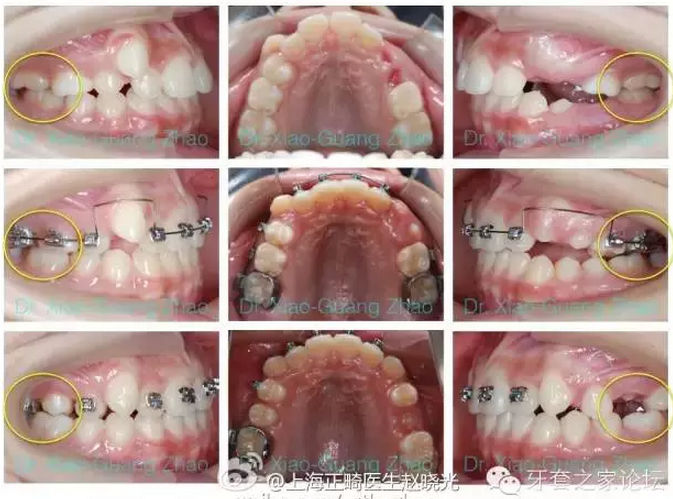

推磨牙向后一般是指推上頜磨牙向后,該技術(shù)在后牙咬合關(guān)系輕度錯(cuò)位,且上前牙存在輕度前突或輕中度擁擠的情況下使用。

如果能在上頜第二磨牙萌出之前開(kāi)始治療,效果能夠更好。

實(shí)現(xiàn)推磨牙向后的方法包括

(一)擺式矯治器結(jié)合固定矯治器,1992年有Hilgers發(fā)明。其特點(diǎn)是效果明顯,但推磨牙向后的作用多來(lái)源于磨牙的向后傾斜,因此比較容易在固定矯治階段復(fù)發(fā)。歡迎參見(jiàn)2005年4月我發(fā)表在“華西口腔醫(yī)學(xué)雜志”上的文章。

(二)口外弓結(jié)合固定矯治器。特點(diǎn)是,如果患者非常好的配合會(huì)有很好的結(jié)果,但是對(duì)于患者配合的依賴性非常強(qiáng)。

(三)支抗種植釘結(jié)合固定矯治器。特點(diǎn)是不依賴患者配合,效果比較肯定,但是有一定的創(chuàng)傷性。

(四)隱形矯治器(結(jié)合頜間牽引或支抗種植釘)。該項(xiàng)技術(shù)中隱形矯治器與傳統(tǒng)的固定矯治器相比有一定優(yōu)勢(shì)。